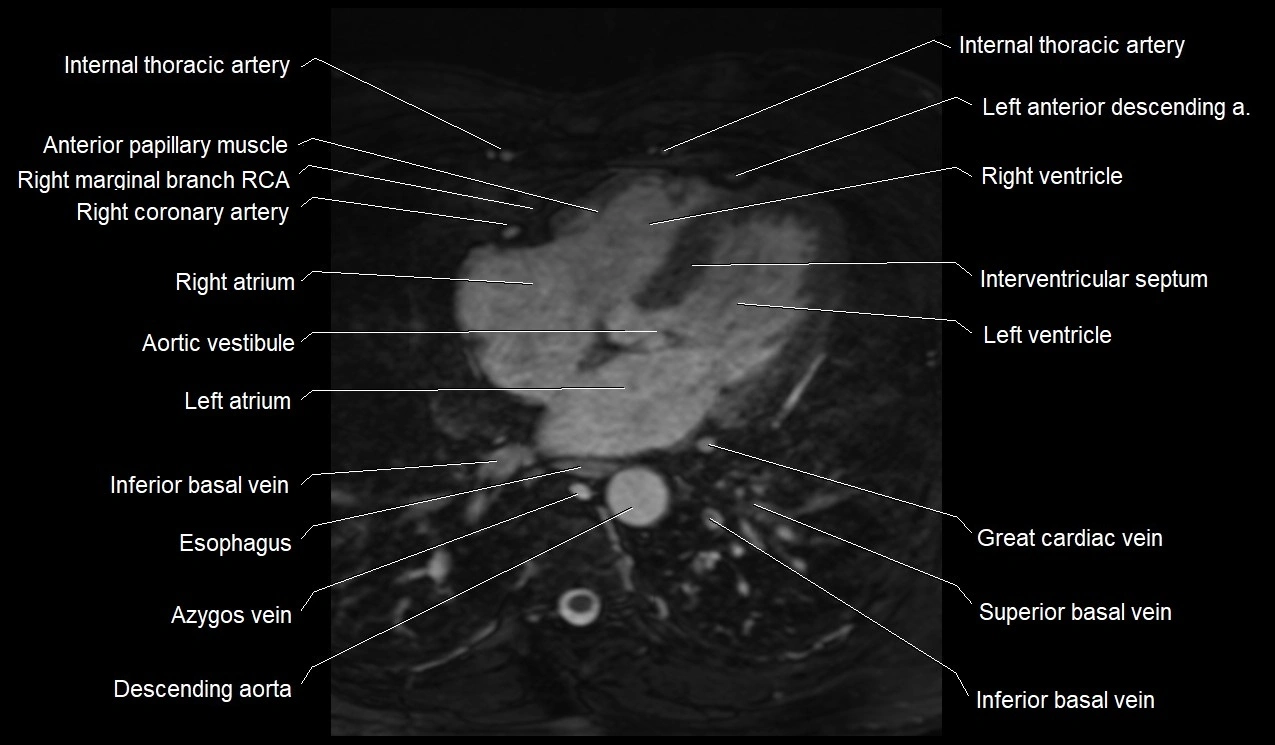

MRI image